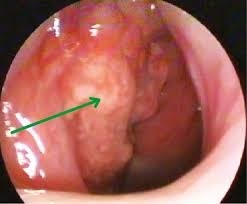

Опухоль быстро увеличивается в размере. На снимках она показывается в виде ярко-красного полипа, который по мере роста округляется и синеет. Через время изменяется форма мягкого неба, а форма верхней челюсти изменяется. У больного становятся выпученными глаза, кровотечения из носа усиливаются, а дыхание носом невозможно.

Признаки злокачественной опухоли носоглотки зависят от направления роста и точного расположения патологического узла. В зависимости от направления роста рак бывает экзофитным, дольчатым, эндофитно-язвенным. В первом случае очаг патологии в своде носоглотки, который быстро разрастается в орбиту и носовую полость. Врач видит четкие границы опухоли, а слизистая оболочка не изменяется. Больной жалуется на кровотечение из носа и сложное дыхание. Эндофитно-язвенная опухоль образуется на задней стенке носоглотки. Она медленно развивается, поэтому носовые выделения слабые. Пациент жалуется на головную боль и снижение остроты слуха с одной стороны. Врач при осмотре выявляет бугорок без четких границ с красной каймой слизистой оболочки. Дольчатая опухоль подразумевает поражение устья слуховой трубы, поэтому снижается слух, а из носа выделяется обильно слизь и кровь. По мере роста новообразования сжимаются черепно-мозговые нервы, в результате чего присоединяется неврологическая симптоматика.

Дифференциальная особенность доброкачественной опухоли заключается в рассмотрении красного новообразования с гладкими стенками посредствам риноскопии. Если опухоль выпирает в ротоглотку, при прикосновении к ней металлическим инструментом она кровоточит. Рентгенография подтверждает разрушение клиновидной кости.

В отличие от юношеской ангеофибромы, злокачественные новообразования проще диагностируются, но из-за позднего обращения к врачу сложно определить точную локализацию опухоли. Аппаратное и инструментальное обследование сводится к следующему:

- фиброскопия с прицельной биопсией с последующим гистологическим и цитологическим анализом;